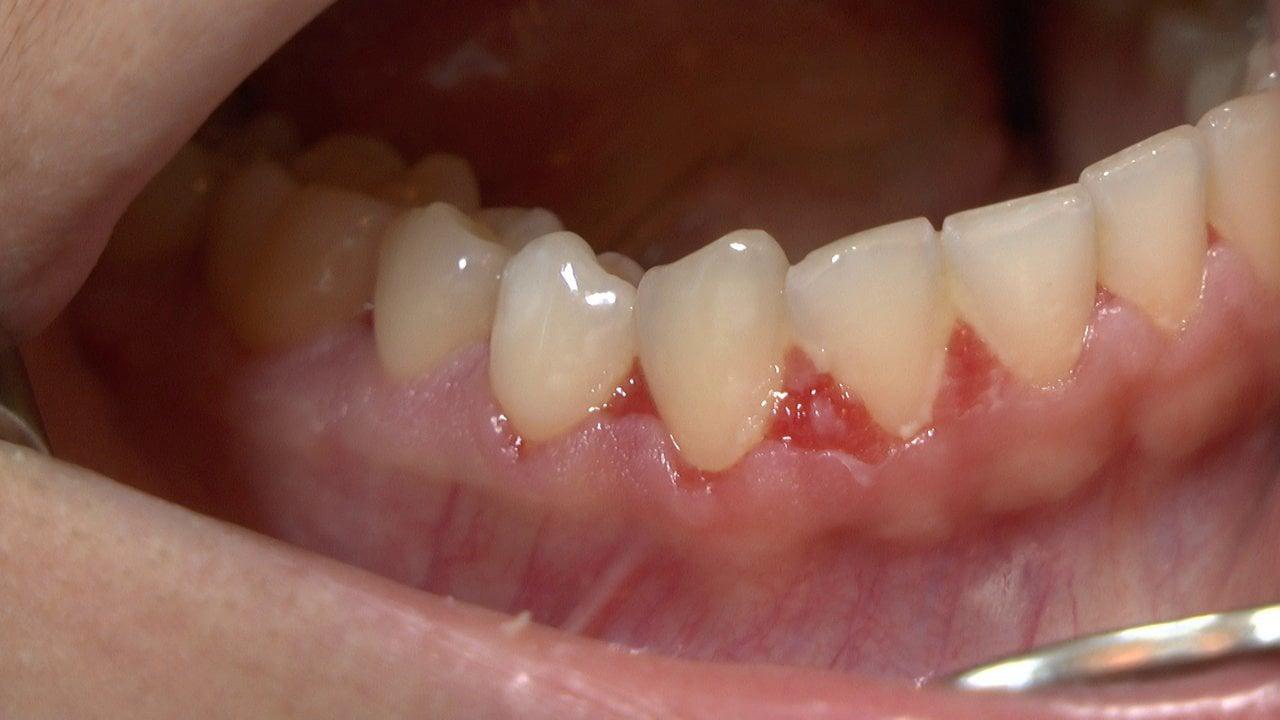

Gingivo-stomatita este o inflamație a gingiilor și a mucoasei bucale care poate provoca durere, sângerare și disconfort la mestecat sau vorbire. În acest articol veți găsi explicații despre semnele frecvente, cauze posibile și măsuri de îngrijire practice pentru ameliorarea simptomelor, precum și indicații despre când este recomandat să solicitați evaluare medicală sau stomatologică. Informațiile sunt generale și nu înlocuiesc consultul unui specialist.

Gingivo‑stomatita este o inflamație a gingiilor și a mucoasei orale care poate varia de la o ușoară roșeață și sensibilitate până la leziuni sau ulcerații dureroase. Afecțiunea poate fi de natură acută sau cronică și, frecvent, generează disconfort la mestecat, vorbire sau igienă orală, influențând calitatea vieții persoanei afectate.

Semnele locale sunt, în general, legate de inflamația mucoasei orale și pot afecta atât gingiile, cât și mucoasa bucală.

• Roșeață și umflare a gingiilor: adesea însoțite de sensibilitate la atingere și senzație de arsură.

• Ulcerații sau vezicule: leziuni dureroase care pot îngreuna mestecarea și vorbirea.

• Sângerare gingivală și durere la periaj: pot apărea la contact sau spontan în formele mai active.